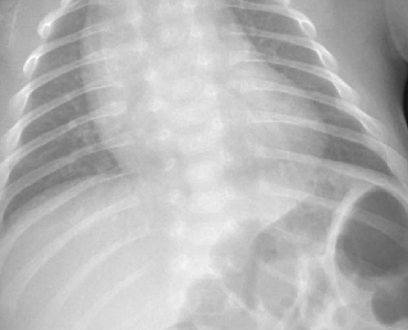

- Neonatal distress caused by a narrowed and bell-shaped thorax

X-rays of the hands, chest, and head are used to diagnose cleidocranial dysostosis in addition to a physical examination. Although it is possible to perform genetic testing to look for mutations in the RUNX2 gene, which is responsible for the condition, this is not typically required to make the initial diagnosis.

- X-ray examination of the bones, particularly the skull, collarbone, and hands.